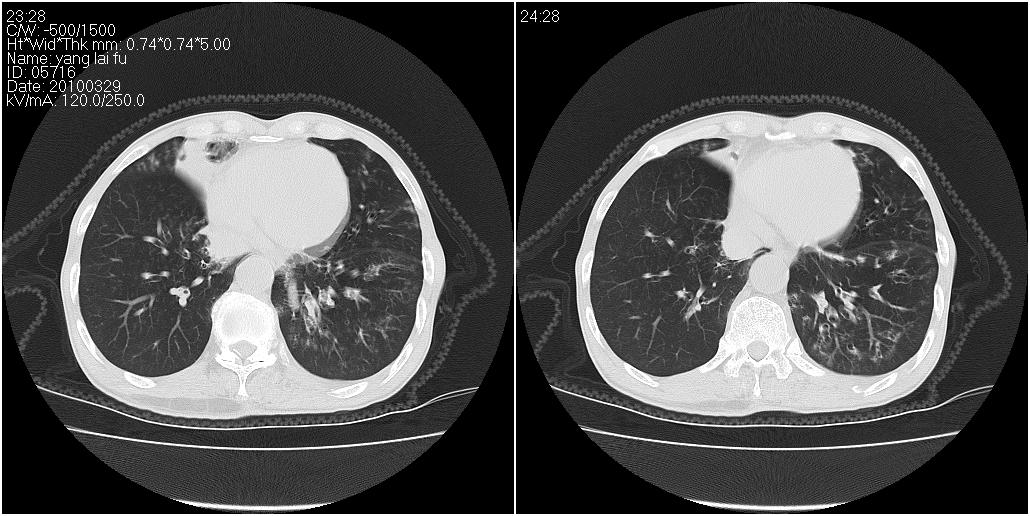

1)右肺中叶慢性炎症并支气管扩张,节段性肺不张。2)两肺下叶支气管扩张。

1)右肺中叶慢性炎症并支气管扩张,节段性肺不张。2)左肺下叶支气管扩张